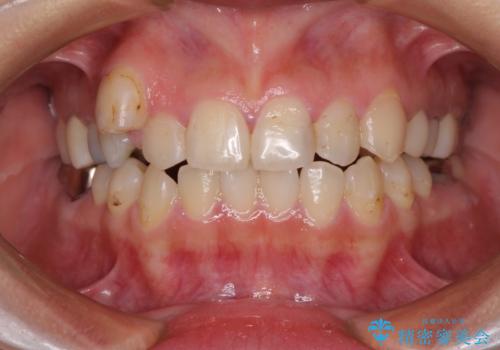

- 歯がほとんどなくなってしまうまで虫歯を放置してしまったとのことで来院された患者様です。

抜歯が必要であることは患者様自身も理解されており、インプラントによる欠損補綴治療を希望されていらっしゃいました。

虫歯を放置した期間が長かったため、対合の下顎大臼歯が上顎に迫ってきており、咬み合わせは非常にシビアでした。

仮歯装着中に頻繁に脱離したため、オールセラミッククラウンは脱離の少ないスクリュータイプとしました。